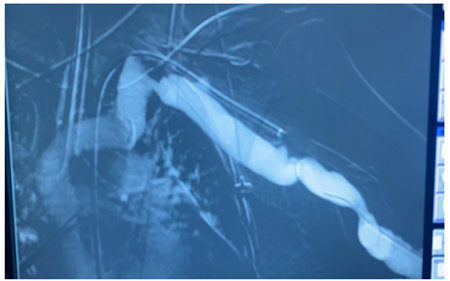

The patient was urgently submitted to an endovascular treatment of the AVF and brachial artery acute thrombosis. Under general anesthesia, a left common femoral artery was retrograde punctured guided with a duplex ultrasound to perform the whole intervention percutaneously with a proper sheat. Then, upper left arm arteriography showed: brachial artery occlusion immediately before stenting, with brachial artery refilling before anastomosis focal venous stenoses. (Figures 1 and 2).

Figure 1: Intraoperative image showing brachial-basilic arteriovenous fistula and a Viabahn occlusion